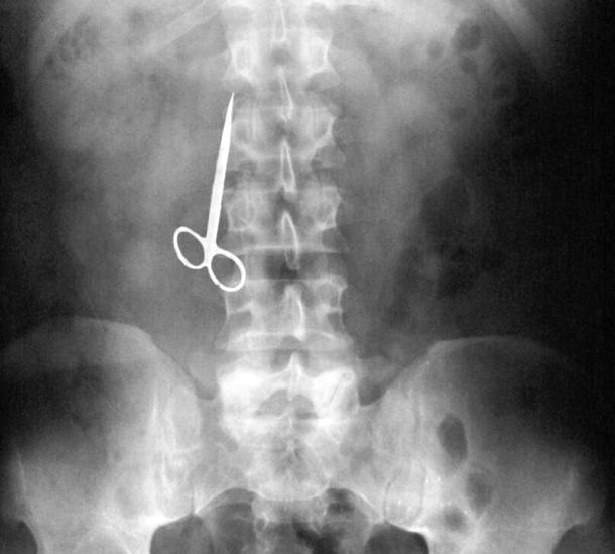

Ingested toothpicks are a relatively rare event, but may cause serious gut injuries with peritonitis, sepsis, or death. The most common causes are debris lodged under the gum line, a lost filling or. I think i swallowed/sucked it into my throat by mistake.

Blog FUAD Informasi Dikongsi Bersama 20 Incredibly Strange XRay Images